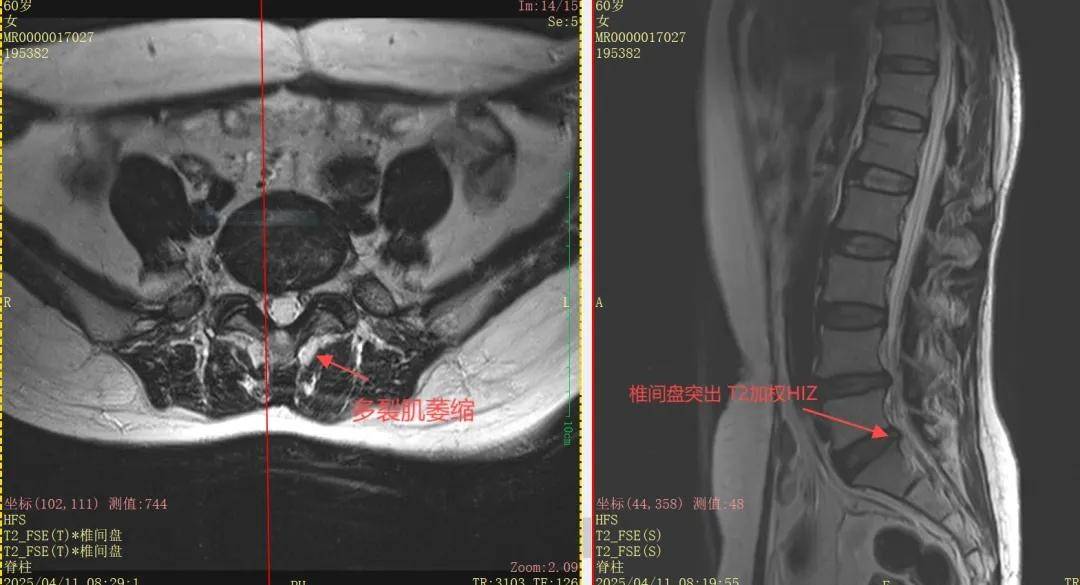

王阿姨腰疼到无法直立,检查却显示腰椎间盘突出但无腿麻症状。叶军博士后团队揪出“真凶”:脊柱两侧多裂肌萎缩并脂肪化!这些本应如“弹簧”般保护腰椎的肌肉一旦退化,椎间盘在压力下直接“暴雷”。